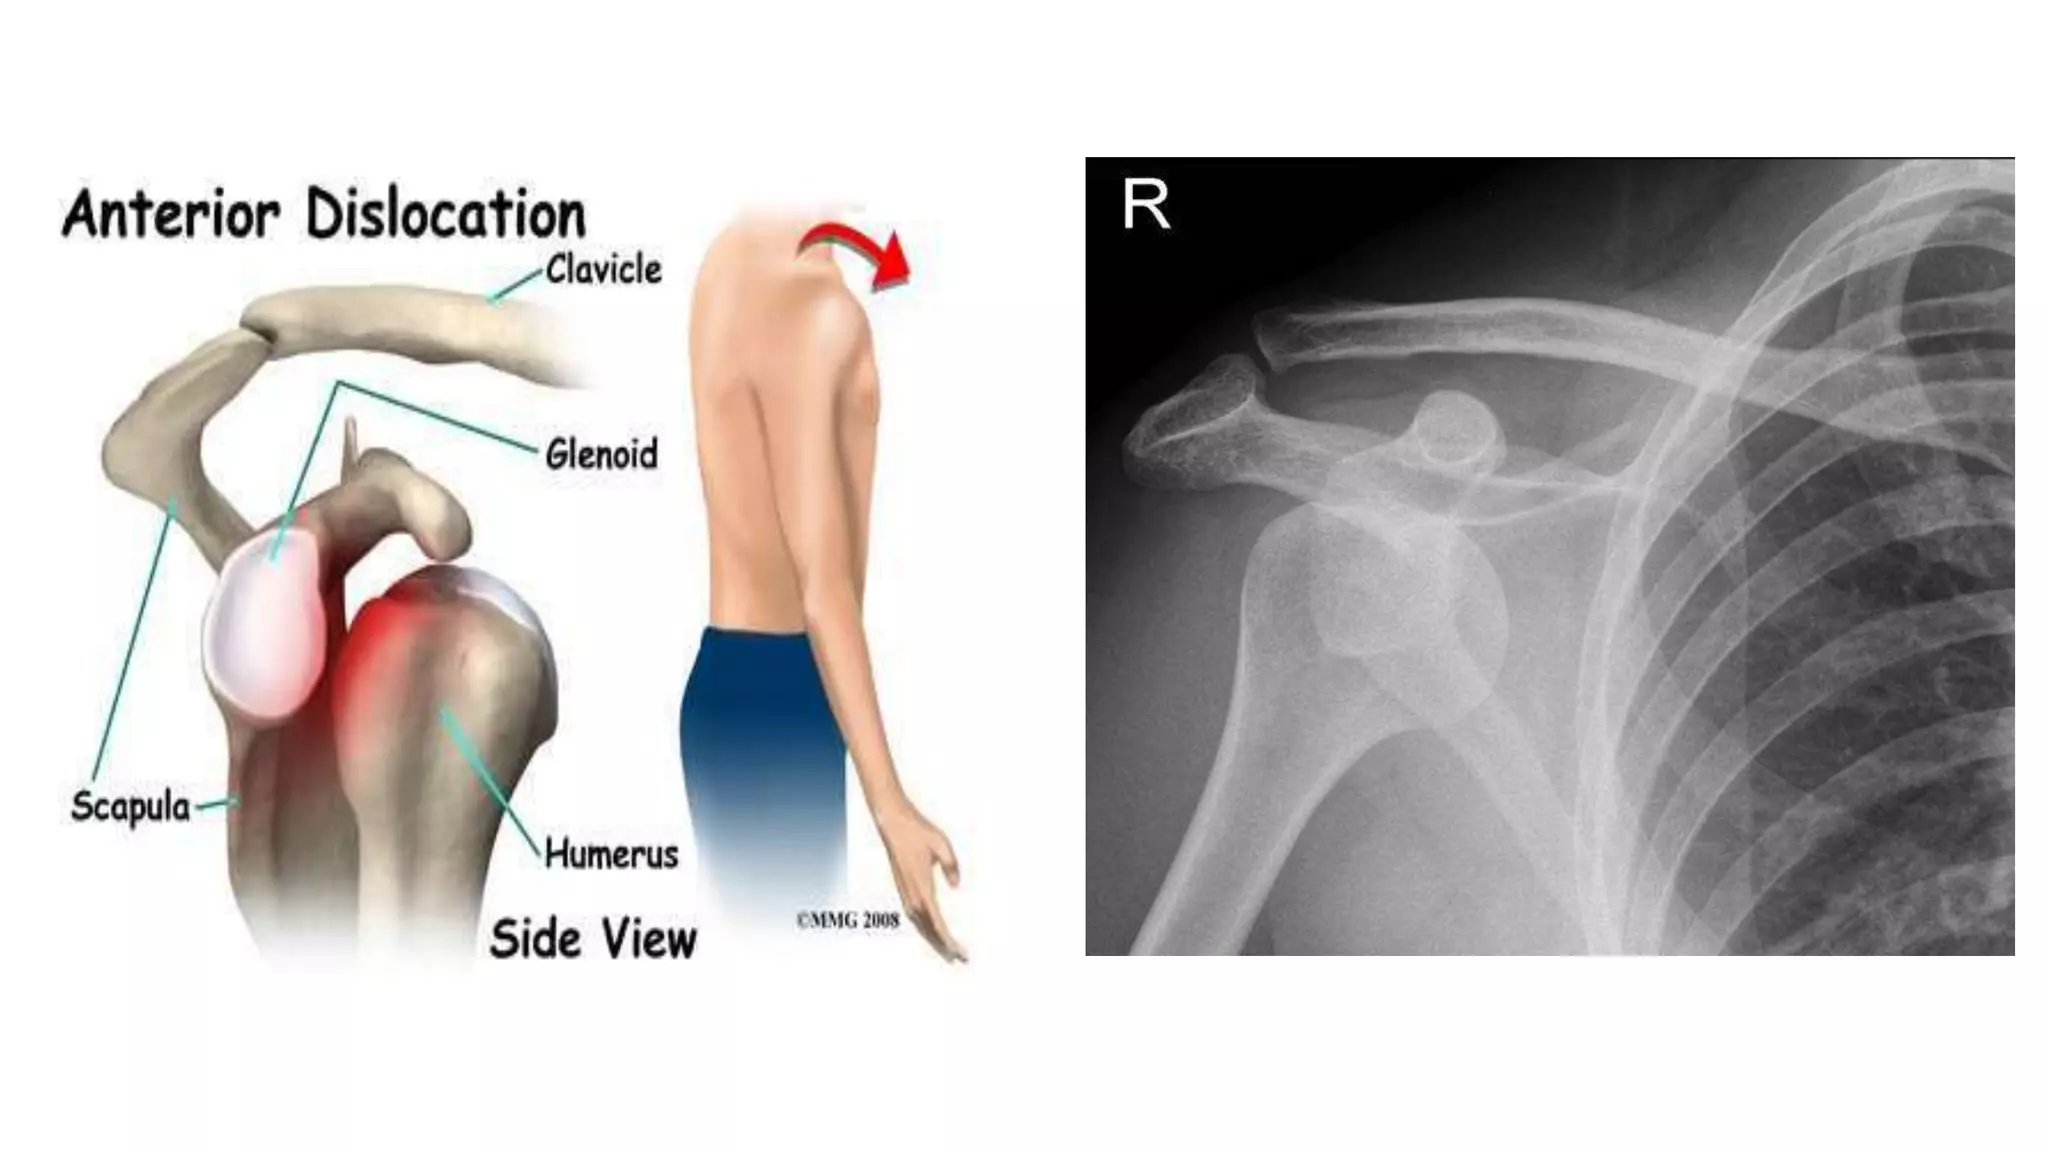

SHOULDER DISLOCATIONS

• anterior > 95%

• posterior 2-4%

• inferior (luxatio erecta) < 1%

MECHANISM OF INJURY

• COMMONEST :Fall on an outstretched hand with shoulder abducted

and externally rotated

PATHOLOGICAL CHANGES IN ANTERIOR DISLOCATION

• BANKART’S LESION

• HILL SACHS LESION

• ROUNDING OFF

• ASSOCIATED INJURIES